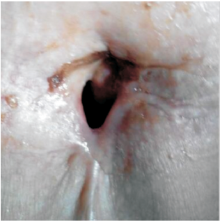

2013年1月患者出现反复呼吸困难。

2013-01-29患者喉部增强CT:喉癌术后, 左侧舌骨术后改变, 与2012-05-18 CT对照, 左侧声带结节状软组织肿块, 考虑喉癌复发可能性大, 见图4和图5, 无病生存期9个月。建议进一步检查。

2013-02-01患者因呼吸困难行气管切开术。

2013-02-25行全喉切除术+左侧颈部淋巴结区域性清扫术, 术后病理:(全喉)鳞状细胞癌, 高分化。肿瘤最大径约1.6 cm; 肿瘤主体位于左侧声门下, 并累及右侧声门; 可见神经束膜侵犯; 肿瘤紧邻周边切缘。淋巴结反应性增生, 未见癌(0/3)。

诊断:左侧声门型鳞状细胞癌术后局部复发rT4aN0M0 Ⅳ a期。